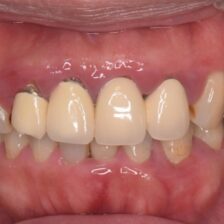

歯科医師、歯科衛生士ともに、マイクロスコープを使用

細部まで妥協しない

精密で、高品質な歯科医療

ダイレクトボンディングなどの

審美治療も高精度に対応

肉眼では見えない細かな部分まで拡大して確認できるため、削りすぎを防ぎ、再発リスクを抑えた質の高い治療が可能です。

治療だけでなく、歯科衛生士による予防・メンテナンスにもマイクロスコープを活用し、細部まで丁寧にケアを行っています。

当院では、カリーナシステムを活用し、治療前・治療中・治療後の状態を静止画や動画で記録。実際の映像を一緒に見ながら、分かりやすく丁寧にご説明します。